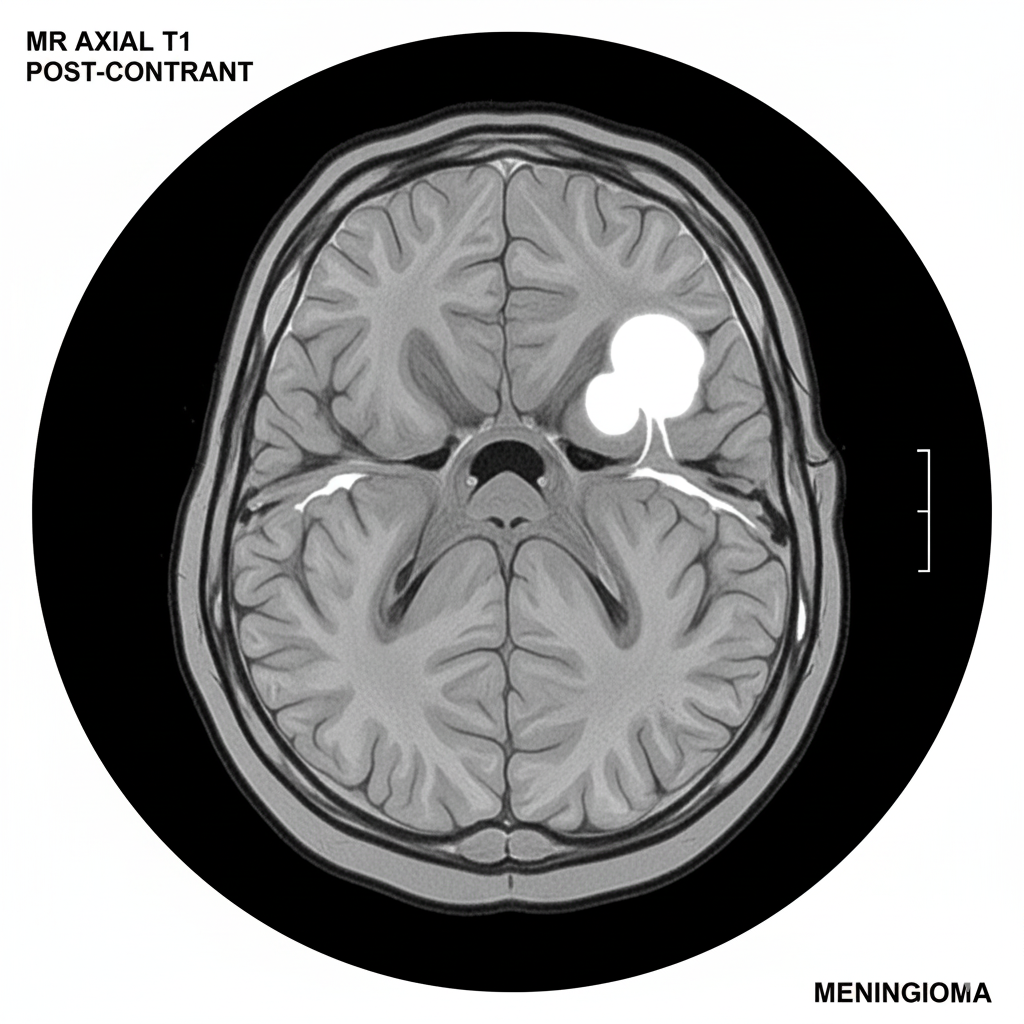

The Role of MRI in Diagnosing Meningiomas

Magnetic Resonance Imaging (MRI) is the primary and most effective tool for diagnosing a meningioma. An MRI of the brain, often with a gadolinium contrast agent, provides a detailed, high-resolution image that can clearly show the tumor’s size, shape, and exact location. The contrast agent is particularly important because it makes the tumor “light up” brightly on the scan, distinguishing it from the surrounding healthy brain tissue. A classic sign of a meningioma on an MRI is its attachment to the dura mater, often with a characteristic “dural tail” sign. The precise information provided by an MRI is essential for a neurologist or neurosurgeon to determine the best course of treatment, whether it be observation, surgery, or radiation.

What is the “dural tail” sign on an MRI?

The “dural tail” is a radiographic sign seen on a contrast-enhanced MRI, which appears as a thickened, enhancing area of the dura mater extending away from the main body of the tumor. It is a classic sign of a meningioma.